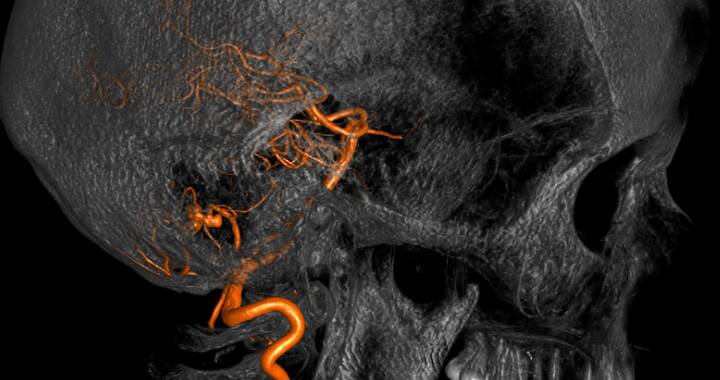

Aneurysmen

Aneurysmen sind Gefäßaussackungen an hirnversorgenden Arterien, die sich häufig im Bereich der Verzweigungen von Hirnbasisarterien befinden. Im Laufe der Zeit können diese Aneurysmen an Größe zunehmen (wachsen) und durch Druck auf Gehirn bzw. Hirnnerven zu neurologischen Symptomen führen. Kommt es zu einer Ruptur („Platzen“) des Aneurysmas, liegt eine lebensbedrohliche Notfallsituation vor und die daraus resultierende Hirnblutung (Subarachnoidalblutung) endet nicht selten tödlich oder führt zu schwerer Behinderung mit lebenslanger Pflegebedürftigkeit.

Ein Aneurysma, das bereits geblutet hat, sollte genau wie ein Aneurysma, das Beschwerden hervorruft und solche, die mit der Zeit eine Wachstumstendenz zeigen, behandelt werden. Bei zufällig entdeckten Aneurysmen muss man die Risiken des Aneurysmas gegen die der Behandlung abwägen. Um eine Blutung oder eine erneute Blutung zu verhindern, muss das Aneurysma von der Blutversorgung „abgeschnitten“ bzw. „ausgeschaltet“ werden. Dies kann erreicht werden, indem in mikrochirurgischer Technik der knöcherne Schädel und die Hirnhäute eröffnet werden und von außen ein Titan-Clip auf den Hals des Aneurysmas gesetzt und so die Verbindung zum Blutgefäßsystem unterbunden wird. Diese Methode nennt man operatives Clipping.

Eine andere Möglichkeit ist die sogenannte endovaskuläre Coil-Embolisation, eine Intervention durch die Abteilung für Neuroradiologie, bei dem das Aneurysma mittels eines Katheters über die Leistenarterie von innen mit Platinspiralen ausgefüllt wird. Erscheint eine Behandlung nicht sinnvoll, muss die Form und Größe des Aneurysmas regelmäßig durch bildgebende Untersuchungen kontrolliert werden.